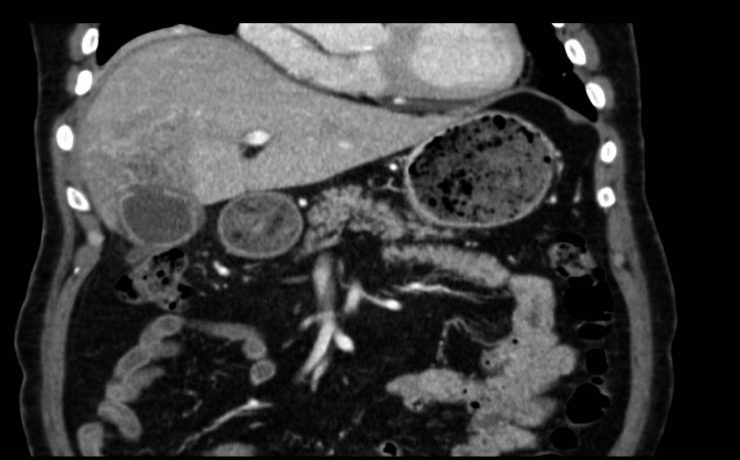

Enfermedad litiásica biliar

La formación de concreciones sólidas en la vesícula o la vía biliar a consecuencia de alteraciones en la composición de la bilis y la motilidad de la vesícula se denomina litiasis biliar. La litiasis biliar es la responsable de la mayor parte de la patología asociada a la vesícula y